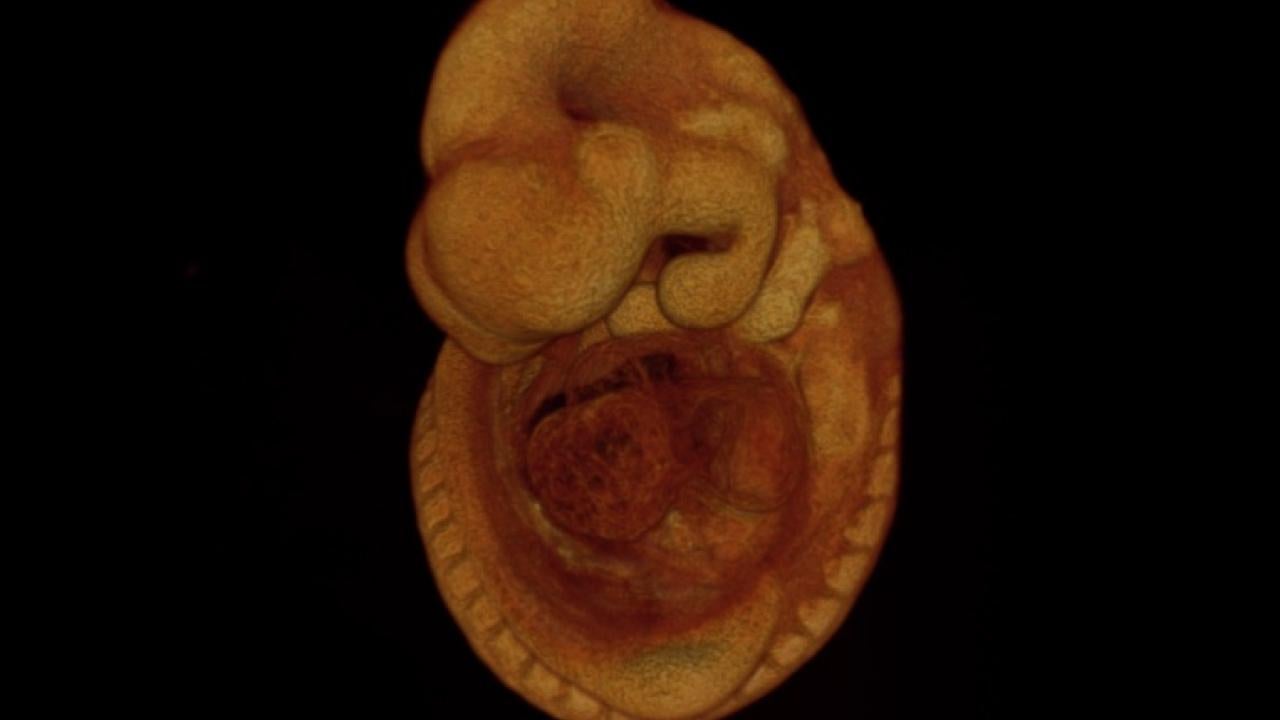

High-resolution computed tomography image of a 9 1/2-day-old mouse embryo. Using advanced imaging techniques, an international team including UC Davis researchers has been able to work out the function of hundreds of genes that are essential to develop a live mouse. Because these genes have human equivalents, they could be used to home in on important genes to study in human diseases. Image: Doug Rowland, UC Davis.

Using high-resolution 3D imaging and automated, computational analysis of the images, the researchers established for each gene both the time of embryonic death and why the embryos died, shedding light on the function of these genes.